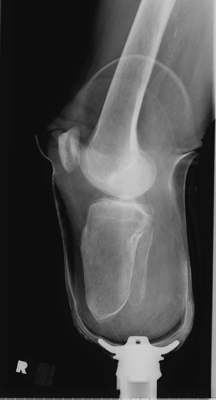

The images shown demonstrates a BKA of acceptable length. The patient is

wearing a prosthesis.